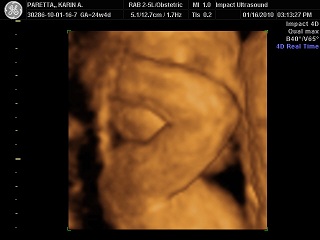

24+4 with my son Chat Icon

I had a 2D/3D sono last night with my daughter (17 weeks) and it was near impossible to see anything.

Image Attachment(s):

Message edited 8/17/2012 12:11:21 PM.